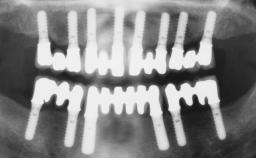

Immediate Loading of Six Implants in the Maxilla and Final Restoration with a Full-Arch Gold/Ceramic FDP Involving the Concept of Tilted Implants

A 61-year-old male patient with a failing fixed maxillary rehabilitation and a fixed mandibular rehabilitation requested a new fixed maxillary rehabilitation. The patient was wearing a temporary metal-reinforced maxillary bridge inserted two years before the consultation. He reported that his previous dentist did not want to insert a definitive framework because he considered the residual teeth to have a negative prognosis. The patient reported a history of recurrent caries and endodontic complications as the main reason for the previous extractions. The anamnesis was negative for periodontal disease and bruxism. The patient’s chief compliant was the mobility of his maxillary prosthesis, which needed to be re-cemented frequently, and discomfort during chewing.Moreover, the patient was not satisfied with the esthetic appearance of his maxillary teeth, which he found too long. The patient asked for a stable and comfortable fixed maxillary rehabilitation and firmly rejected any removable solution.

# of Implants 6

Type of Implants One-Piece|Reduced-Diameter